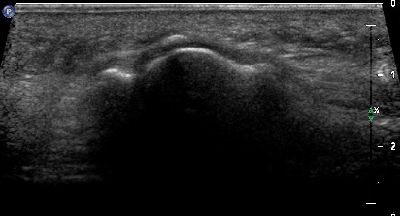

Ipoplasia dei sesamoidi del primo dito (img. 01) Ipoplasia dei sesamoidi del primo dito (img. 01)